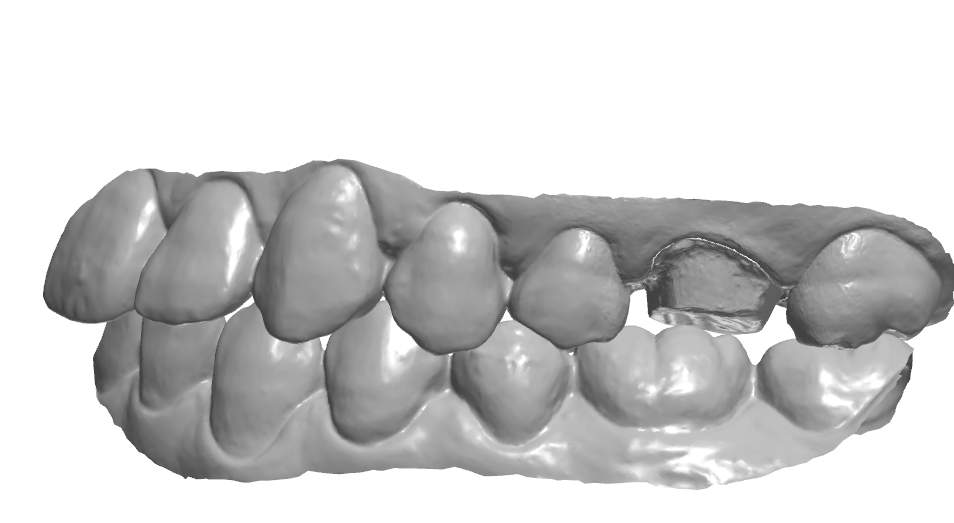

치은 라인의 연속성 체크.

치은 라인가 치간 사이 엠브레져 체크.

보이는 방향에 따라 모양이 달라 보인다.

1치대2치 관계

치아의 수평피개 체크

각 치아의 풍융도 체크.